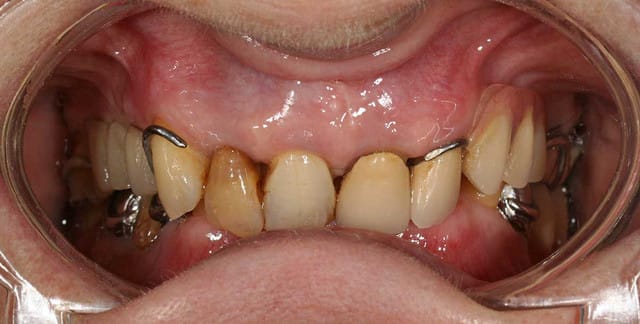

cette patiente que je soigne a des PPA plus adaptées :

bascule antérieure de la prothèse sup qui lui blesse les gencives derrière les 13 et 22

la 35 présente une lésion endo/paro et une mobilité importante me semblant justifier l'avulsion

le premier truc qui m'est passé par la tete a été de faire de la prothèse combinée (après son refus des implants) en couronnant les 5 antérieures avec des contournements fraisés pour éviter la bascule et des attachements pour éviter les crochets

mais quand on y regarde d'un tout petit peu plus près ... ça me semble difficile !

n'hésitez pas à donner quelques idées à un jeune qui se demande bien quoi faire.